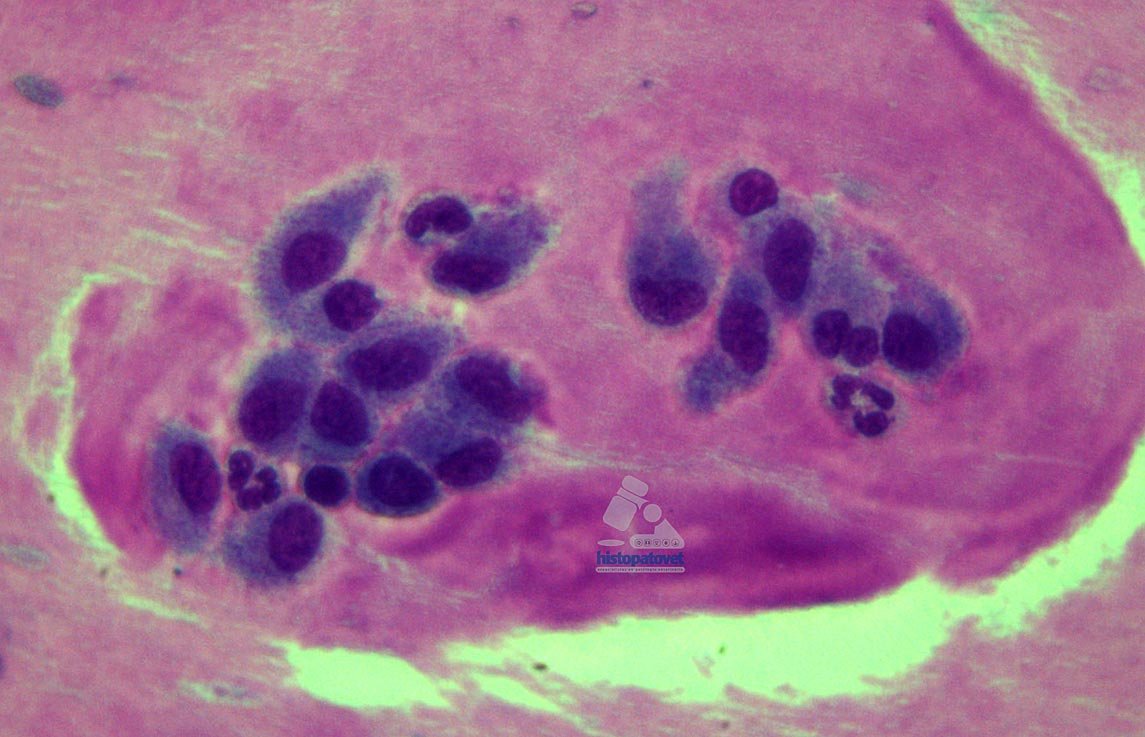

La citología no ha probado ser buena herramienta, hay trabajos que reportan un 50 % de certeza. Ver. Fig.2.

El principal hallazgo histopatológico es encontrar especialmente en la periferia del tumor una respuesta inflamatoria sobre todo a base de linfocitos y macrófagos. Estos últimos fagocitando algún material extraño, que generalmente son remanentes de la vacuna o aluminio (coadyuvante). Ver las siguientes tres figuras(3,4,5).